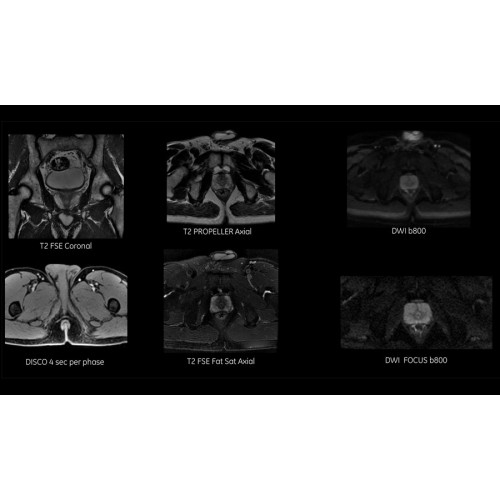

МРТ аппарат GE SIGNA Voyager 1.5T позволяет проводить полный спектр магнитно-резонансных исследований, включая нейровизуализацию, исследования опорно-двигательного аппарата, органов брюшной полости и малого таза, а также специализированные кардиологические программы.

• Обследования органов брюшной полости и малого таза